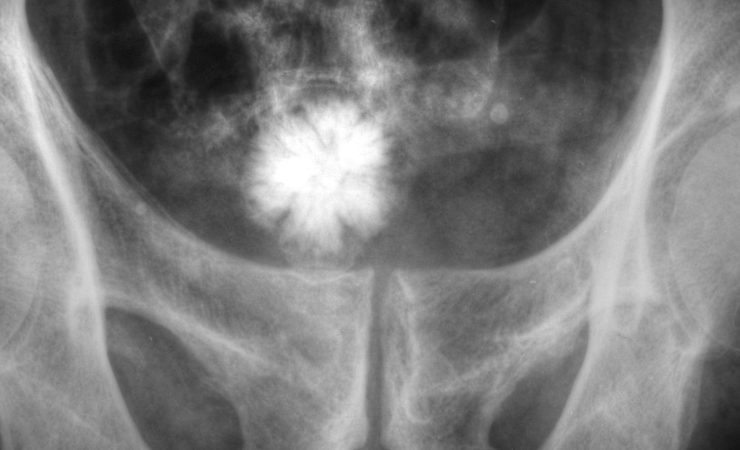

Cos’è l’ipertrofia prostatica?

Questi sintomi indicano l’ingrandimento della prostata a discapito dell’uretere, cioè il canale che consente all’urina di passare dalla vescica all’esterno del corpo.

Nei paesi occidentali dopo i 70 anni l’ipertrofia prostatica si presenta in forme più o meno accentuate nell’80% degli uomini; ecco perché è importante prevenire il più possibile!

Dai 50 anni in poi (o anche prima nel caso si presentino disturbi nella minzione) è raccomandata una visita urologica, che consisterà principalmente in una esplorazione rettale. Nel caso il medico percepisca un ingrossamento predisporrà i seguenti esami, per escludere la possibilità che l’aumento di volume sia dovuto ad un tumore: